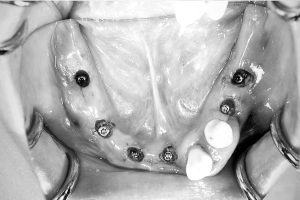

術中

口腔内でサージカルガイトがずれるのを防ぐために、AO4.6では骨にピンでサージカルガイトを固定して行います。